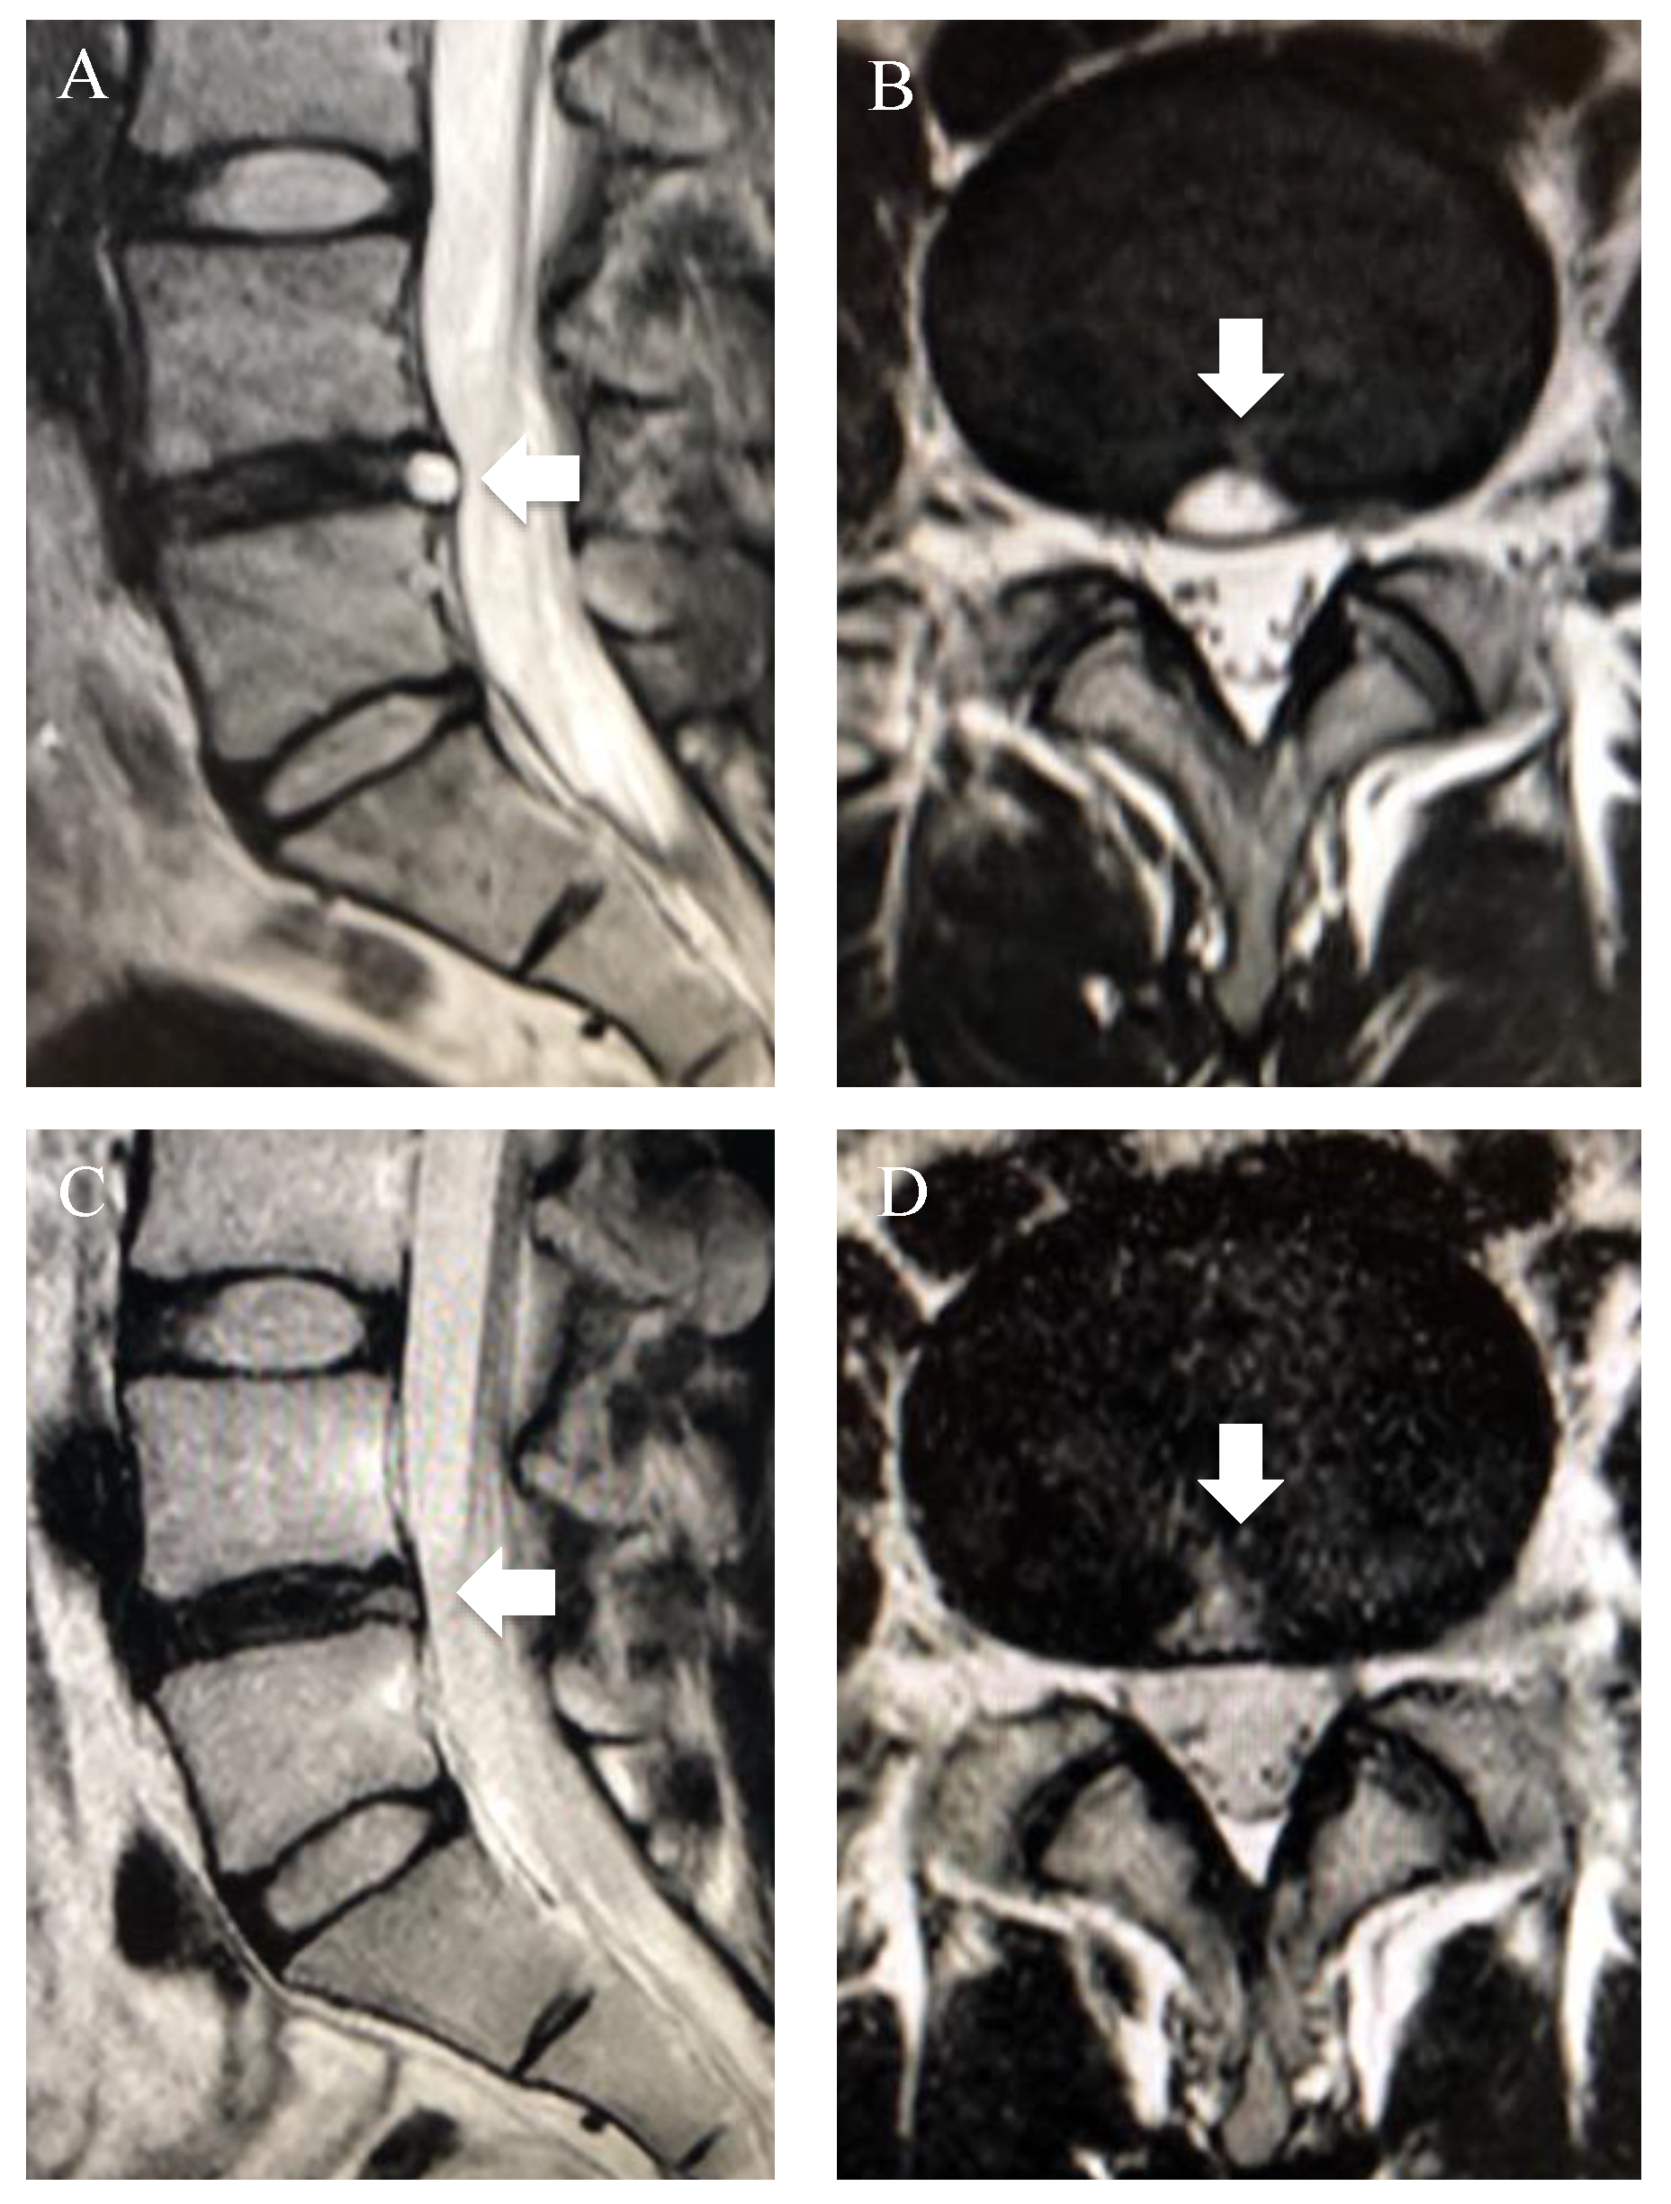

3.4. High-Intensity Zone (HIZ)

- Aprill, C.; Bogduk, N. High-intensity zone: A diagnostic sign of painful lumbar disc on magnetic resonance imaging. Br. J. Radiol. 1992, 65, 361–369. [Google Scholar] [CrossRef] [PubMed]

- Fang, C.; Zhang, W.; Chen, L.; Li, H. The correlation between the high-intensity zone on a T2-weighted MRI and positive outcomes of discography: A meta-analysis. J. Orthop. Surg. Res. 2017, 12, 26. [Google Scholar] [CrossRef] [PubMed][Green Version]

- Jha, S.C.; Higashino, K.; Sakai, T.; Takata, Y.; Abe, M.; Yamashita, K.; Morimoto, M.; Fukuta, S.; Nagamachi, A.; Sairyo, K. Clinical Significance of High-intensity Zone for Discogenic Low Back Pain: A Review. J. Med. Investig. 2016, 63, 1–7. [Google Scholar] [CrossRef] [PubMed]

- Teraguchi, M.; Yim, R.; Cheung, J.P.-Y.; Samartzis, D. The association of high-intensity zones on MRI and low back pain: A systematic review. Scoliosis Spinal Disord. 2018, 13, 22. [Google Scholar] [CrossRef] [PubMed]